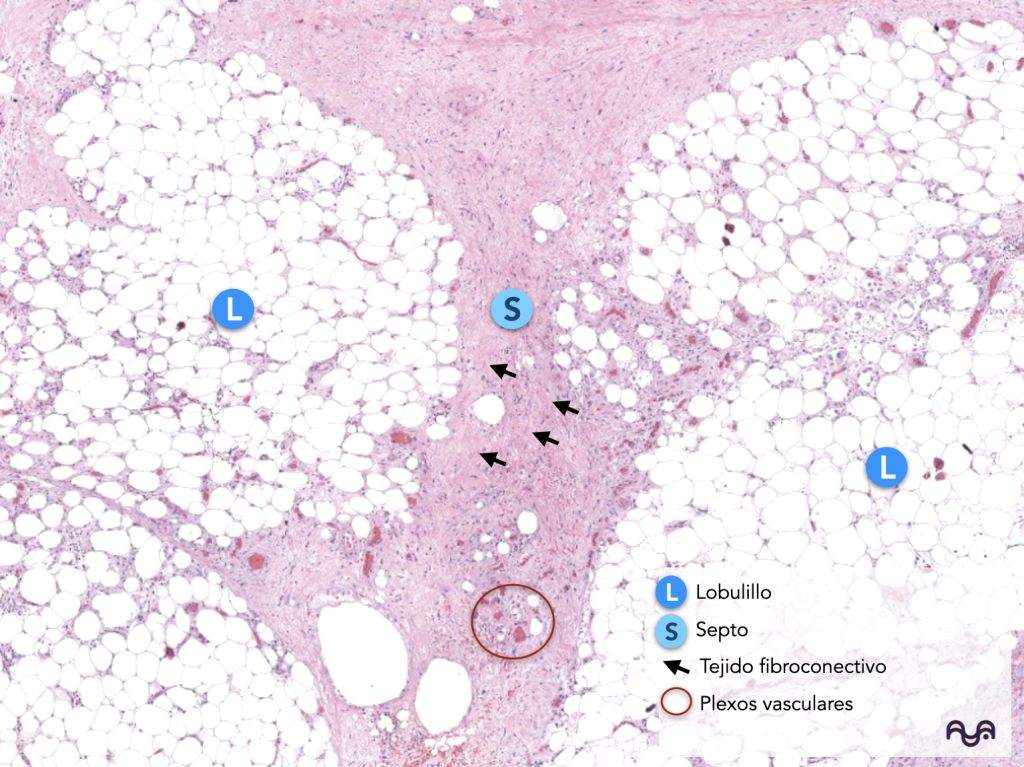

Identificar en H&E: adipocitos, lobulillos, septos fibrosos y paquetes vasculonerviosos. Kim 2023; Estève 2019

La arquitectura típica es lobulillar: lobulillos de grasa separados por septos fibrosos (colágeno) que “organizan” el tejido. Estève 2019

Los septos suelen contener vasos, nervios y, según región, trayectos de anexos profundos. Lopez-Ojeda 2022

2) A aumento intermedio (10×): “lobulillo vs septo”

Lobulillo adiposo: agrupación de adipocitos con poco tejido conectivo entre ellos.

Septo: tejido conectivo más denso, con vasos (luz + pared recubierta de células endoteliales) y a veces nervios (fascículos ondulados con perineurio sutil). Lopez-Ojeda 2022